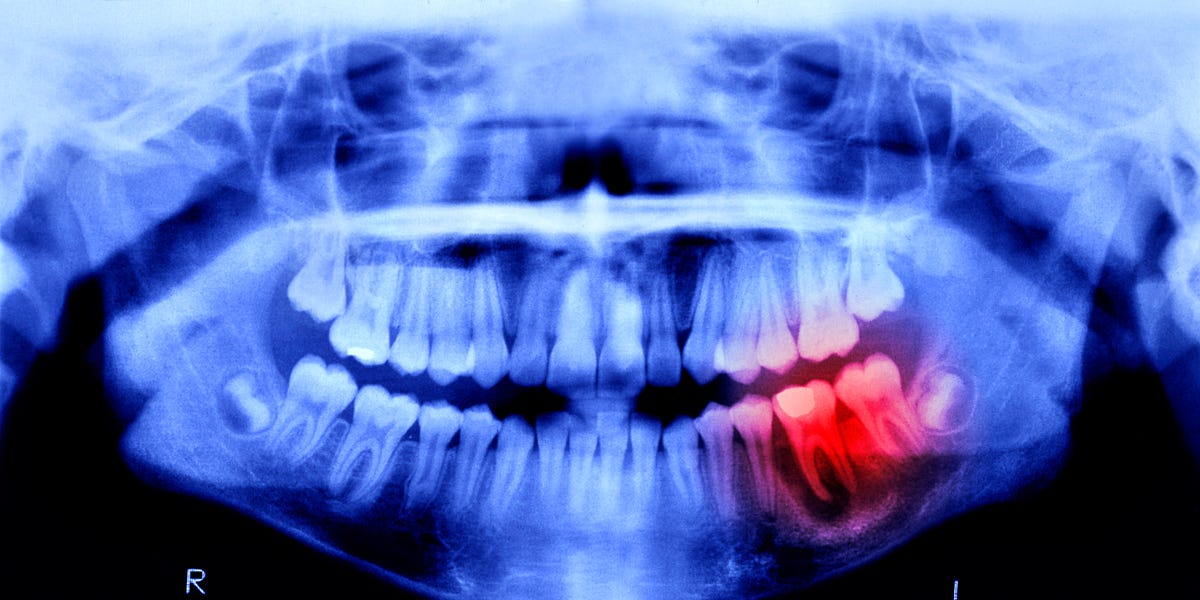

Now, scientists will see just how similar, because humans are undergoing a similar trial. Lasting 11 months, this study focuses on 30 males between the ages of 30 and 64—each missing at least one tooth. The drug will be administered intravenously to prove its effectiveness and safety, and luckily, no side effects have been reported in previous animal studies.

If all goes well, Kitano Hospital will administer the treatment to patients between the ages of 2 to 7 who are missing at least four teeth, with the end goal of having a tooth-regrowing medicine available by the year 2030. While these treatments are currently focused on patients with congenital tooth deficiency, Takahashi hopes the treatment will be available for anyone who’s lost a tooth.